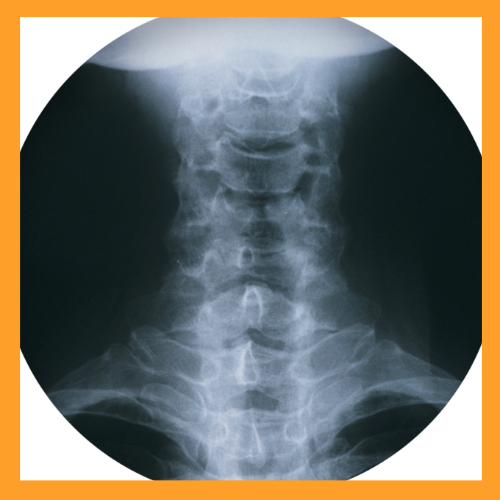

도수치료는 전문 물리치료사가 손이나 신체 일부를 이용해 환자의 근육, 관절, 인대 등을 조작하며 통증을 완화시키고 신체 기능을 회복시키는 비수술적 치료법입니다. 주로 척추 및 관절의 변형을 바로잡고, 근골격계 질환으로 인한 통증을 완화하며, 신경 기능을 회복시키는 데 중점을 둡니다.

도수치료는 근골격계 불균형으로 인해 발생하는 다양한 문제를 해결하기 위해 적용되며, 치료사는 환자의 상태를 진단한 후 개인 맞춤형으로 치료 계획을 수립합니다. 특히 디스크 탈출증, 척추측만증, 만성적인 목과 허리 통증에 효과적입니다.